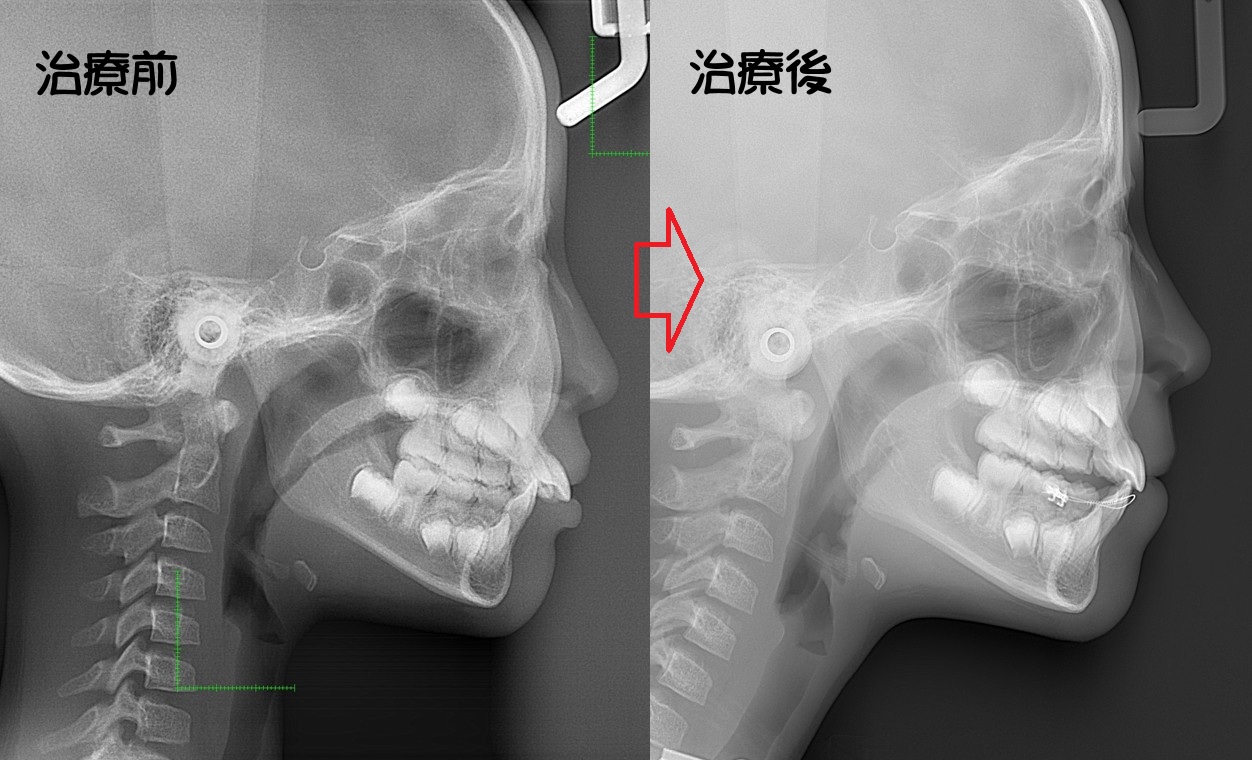

顎変形症:下の歯(顎)が出ている。また、下顎側方偏位:(あごまがり)である

下顎側方偏位:あごまがり

噛んだときに上下の歯が左右にずれているまたは顎が左右にずれている場合、 咬む癖や、小児期の癖、現在かぶせものをしているものの問題等があります。 場合によっては顎の痛みが伴うこともあります。

・下顎側方偏位

・上顎の突出・後退

・下顎骨突出・後退

・顎変形症に伴う顔貌の積極的な改善

・主訴:下あごが出ている。顎が曲がっている。

・診断:骨格性下顎前突

・年齢:20歳

・使用した主な装置:マルチブラケット装置

・抜歯部位:第一小臼歯を4本抜去

・治療期間:30か月

・通院回数:30回

・費用の目安:保険適応。保険矯正代金は、20万円くらい。症状・期間によってかわります。その他大学病院で外科矯正手術代金がかかります。

リスク・副作用:

・前歯の位置を後退させるためにすき間を確保する必要上、歯を減らします。

・骨の移動を行うために入院期間:約2週間・手術代金別途かかります。

・虫歯にならない様に、通常の歯磨きを工夫することが必要です。

・歯が動く際に、歯のゆれを痛みとして感じることがあります。

・根の吸収が起きることがあります。

・保定をしないと後戻りが起きることがあります。